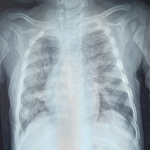

A 20-day-old female late-preterm neonate (34+4 weeks, birth weight: 920 g) born via lower segment cesarean section for breech presentation to a primigravida mother presented with a lumbosacral swelling noted at birth. The neonate cried immediately after delivery. On examination, a dorsally placed cystic swelling with exposed neural placode was observed, consistent with an open neural tube defect. Lower-limb tone was reduced, with poor spontaneous movements and absent anal reflex. No craniofacial anomalies were noted. Magnetic resonance imaging (MRI) of the spine and brain demonstrated a lumbosacral meningomyelocele with herniation of neural elements through a bony defect, along with features of Chiari II malformation, including downward displacement of cerebellar tonsils and a small posterior fossa. The three differential diagnoses included meningocele, terminal myelocystocele, and lipomyelomeningocele. These findings confirmed meningomyelocele with associated Chiari II malformation. Screening cranial ultrasound showed mild ventriculomegaly. The neonate was managed in the neonatal intensive care unit (NICU) with a sterile dressing of the lesion, prone positioning, infection prevention measures, and fluid/electrolyte monitoring. Neurosurgical repair of the defect was planned (or completed on the day after birth). Supportive physiotherapy included positioning, maintaining skin integrity, and monitoring lower-limb responses. Postoperatively, the neonate remained hemodynamically stable with no immediate surgical complications. Neurological status and head circumference are being monitored for potential development of hydrocephalus.